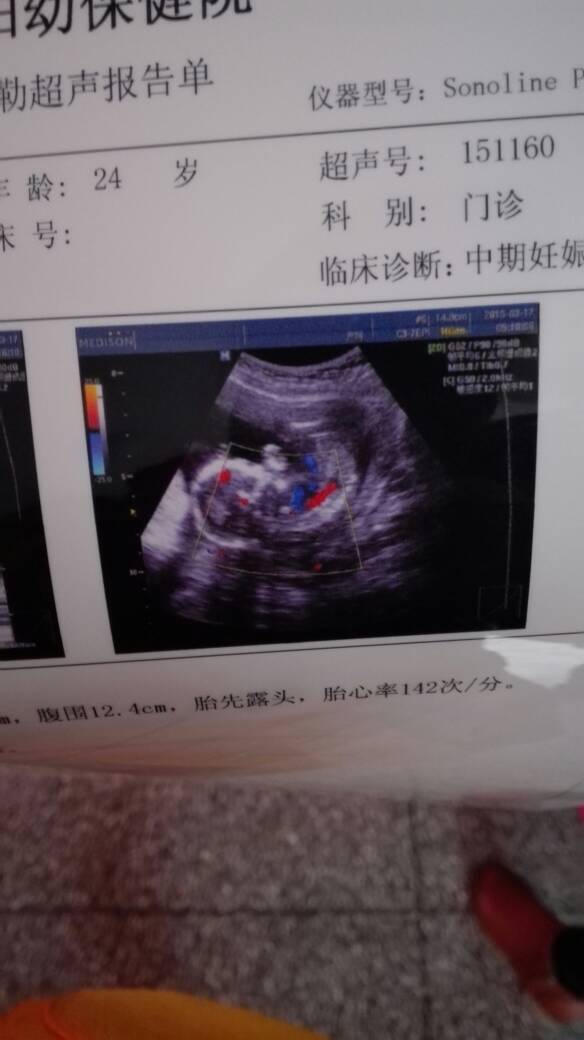

谁帮我看看男孩女孩阿 谁帮我看看男孩女孩阿 点击展开 151*****886_j1OX 2015-03-24 18:18 为您推荐: 其他回答 不清楚,,,,, 王若沁 2015-03-24 20:38 男女都是宝 倾城_Kzsy 2015-03-24 19:55 看不出来, 习惯,习惯 2015-03-24 19:18 看不出来, 美🐑 2015-03-24 18:55 看不出来'' 138*****382_N3Ui 2015-03-24 18:46 加载更多 相关问题 宝妈们帮我看看是男孩女孩???已经有男宝了 我怀孕38天,孕囊是19*14帮我看看是男孩女孩阿? 我怀孕38天,孕囊是19*14帮我看看是男孩女孩阿?